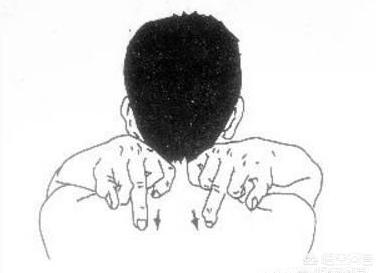

3.肺を活性化する作用

こめかみのあたりで肺をたたく(慣用句);fig. 肺のツボをたたく毎晩寝る前に椅子に座り、両膝を自然に離し、両手を太ももの上に置き、頭を閉じ、全身をリラックスさせ、丹田を守ることを意識する。

胸に息を吸い込み、両手を中空拳に握り、肺兪のツボ(第3胸椎の後方、棘突起の下、指幅2本の開口部の左右横の位置)の裏を数十回たたき、同時に手のひらで下の裏の両側から上に向かって軽く撫でるように10分ほど挙げる。

この方法は、気の胸をリラックスさせ、健康な肺の効果を持ち、痰の排出を助け、脊椎の経絡を通過することができ、風邪を予防することができます。

1.肝臓と胆嚢の経絡を叩く

肝経をノックして肝気のブロックを解除し、肝気がクリアになると、すべての静脈がクリアになる。

寝た姿勢で両足を少し上げ、足の手のひらを向かい合わせにする。

麺棒を手に持ち、太ももの付け根から、膝の関節の前までゆっくりと叩く。

片側を叩いたら、もう片方の手で麺棒を持ち、もう片方の足の同じ部分を叩く。

タッピングするときは、両足に同じ時間、同じ力加減を保つ。

左右交互に10分ほど叩くと、肝経の詰まりを効果的に取り除くことができる。